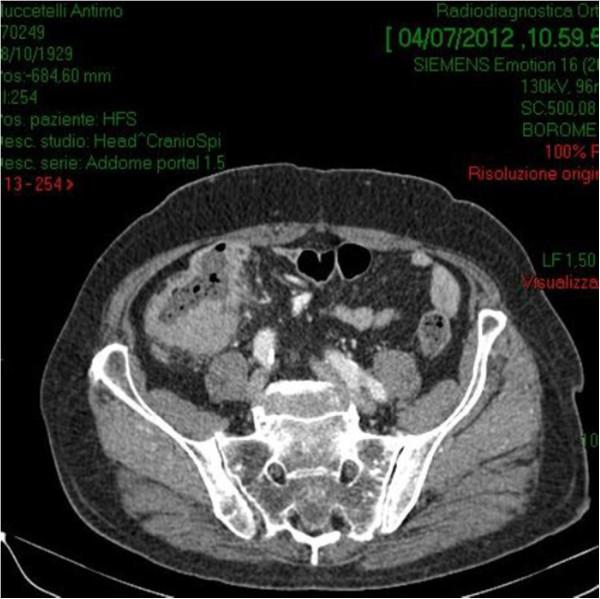

A 70-year-old male with a 6-mo history of vague abdominal pain, constipation and melena was referred to our hospital. Computed tomography scan of abdomen revealed the presence of a mass along the proximal ascending colon. Colonoscopy biopsy showed external compression of the cecum with two ulcerations of mucosa, but it was not consistent for a definitive diagnosis. Because the difficulties in the preoperative pathological diagnosis, the high risk of bowel obstruction and the correlated hemorrhagic risk, the patient underwent a right hemicolectomy associated with locoregional lymphadenectomy and liver resection.The surgically resected right colon and liver tumors were all immunohistochemically diagnosed as diffuse large B-cell lymphomas (DLBCL). The patient refused any other antineoplastic treatment; he is alive and free of disease at 3 years after initial diagnosis.

一名70岁男性,有6个月的腹部隐痛、便秘和黑便病史,转诊至我院。腹部计算机断层扫描显示升结肠近端有一肿块。结肠镜活检显示盲肠受外部压迫,黏膜有两处溃疡,但这并不足以确诊。由于术前病理诊断困难、肠梗阻风险高以及相关出血风险,患者接受了右半结肠切除术,同时行局部淋巴结清扫和肝切除术。手术切除的右结肠和肝肿瘤经免疫组织化学诊断均为弥漫性大B细胞淋巴瘤(DLBCL)。患者拒绝任何其他抗肿瘤治疗;初次诊断3年后仍存活且无疾病复发。